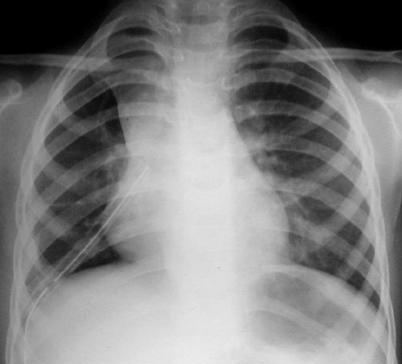

Radiología del tórax

• Rx. tórax PA: Observamos lesiones quísticas múltiples en base pulmonar derecho, aumento del volumen pulmonar a predominio basal derecho con mayor transparencia y discreta desviación contra lateral del mediastino.

• Rx. tórax lateral: Se aprecia mayor transparencia pulmonar y lesiones quísticas múltiples en todos los segmentos correspondientes al lóbulo pulmonar inferior derecho.

• No se observan lesiones de atelectasia, nódulos pulmonares ni adenopatias del mediastino